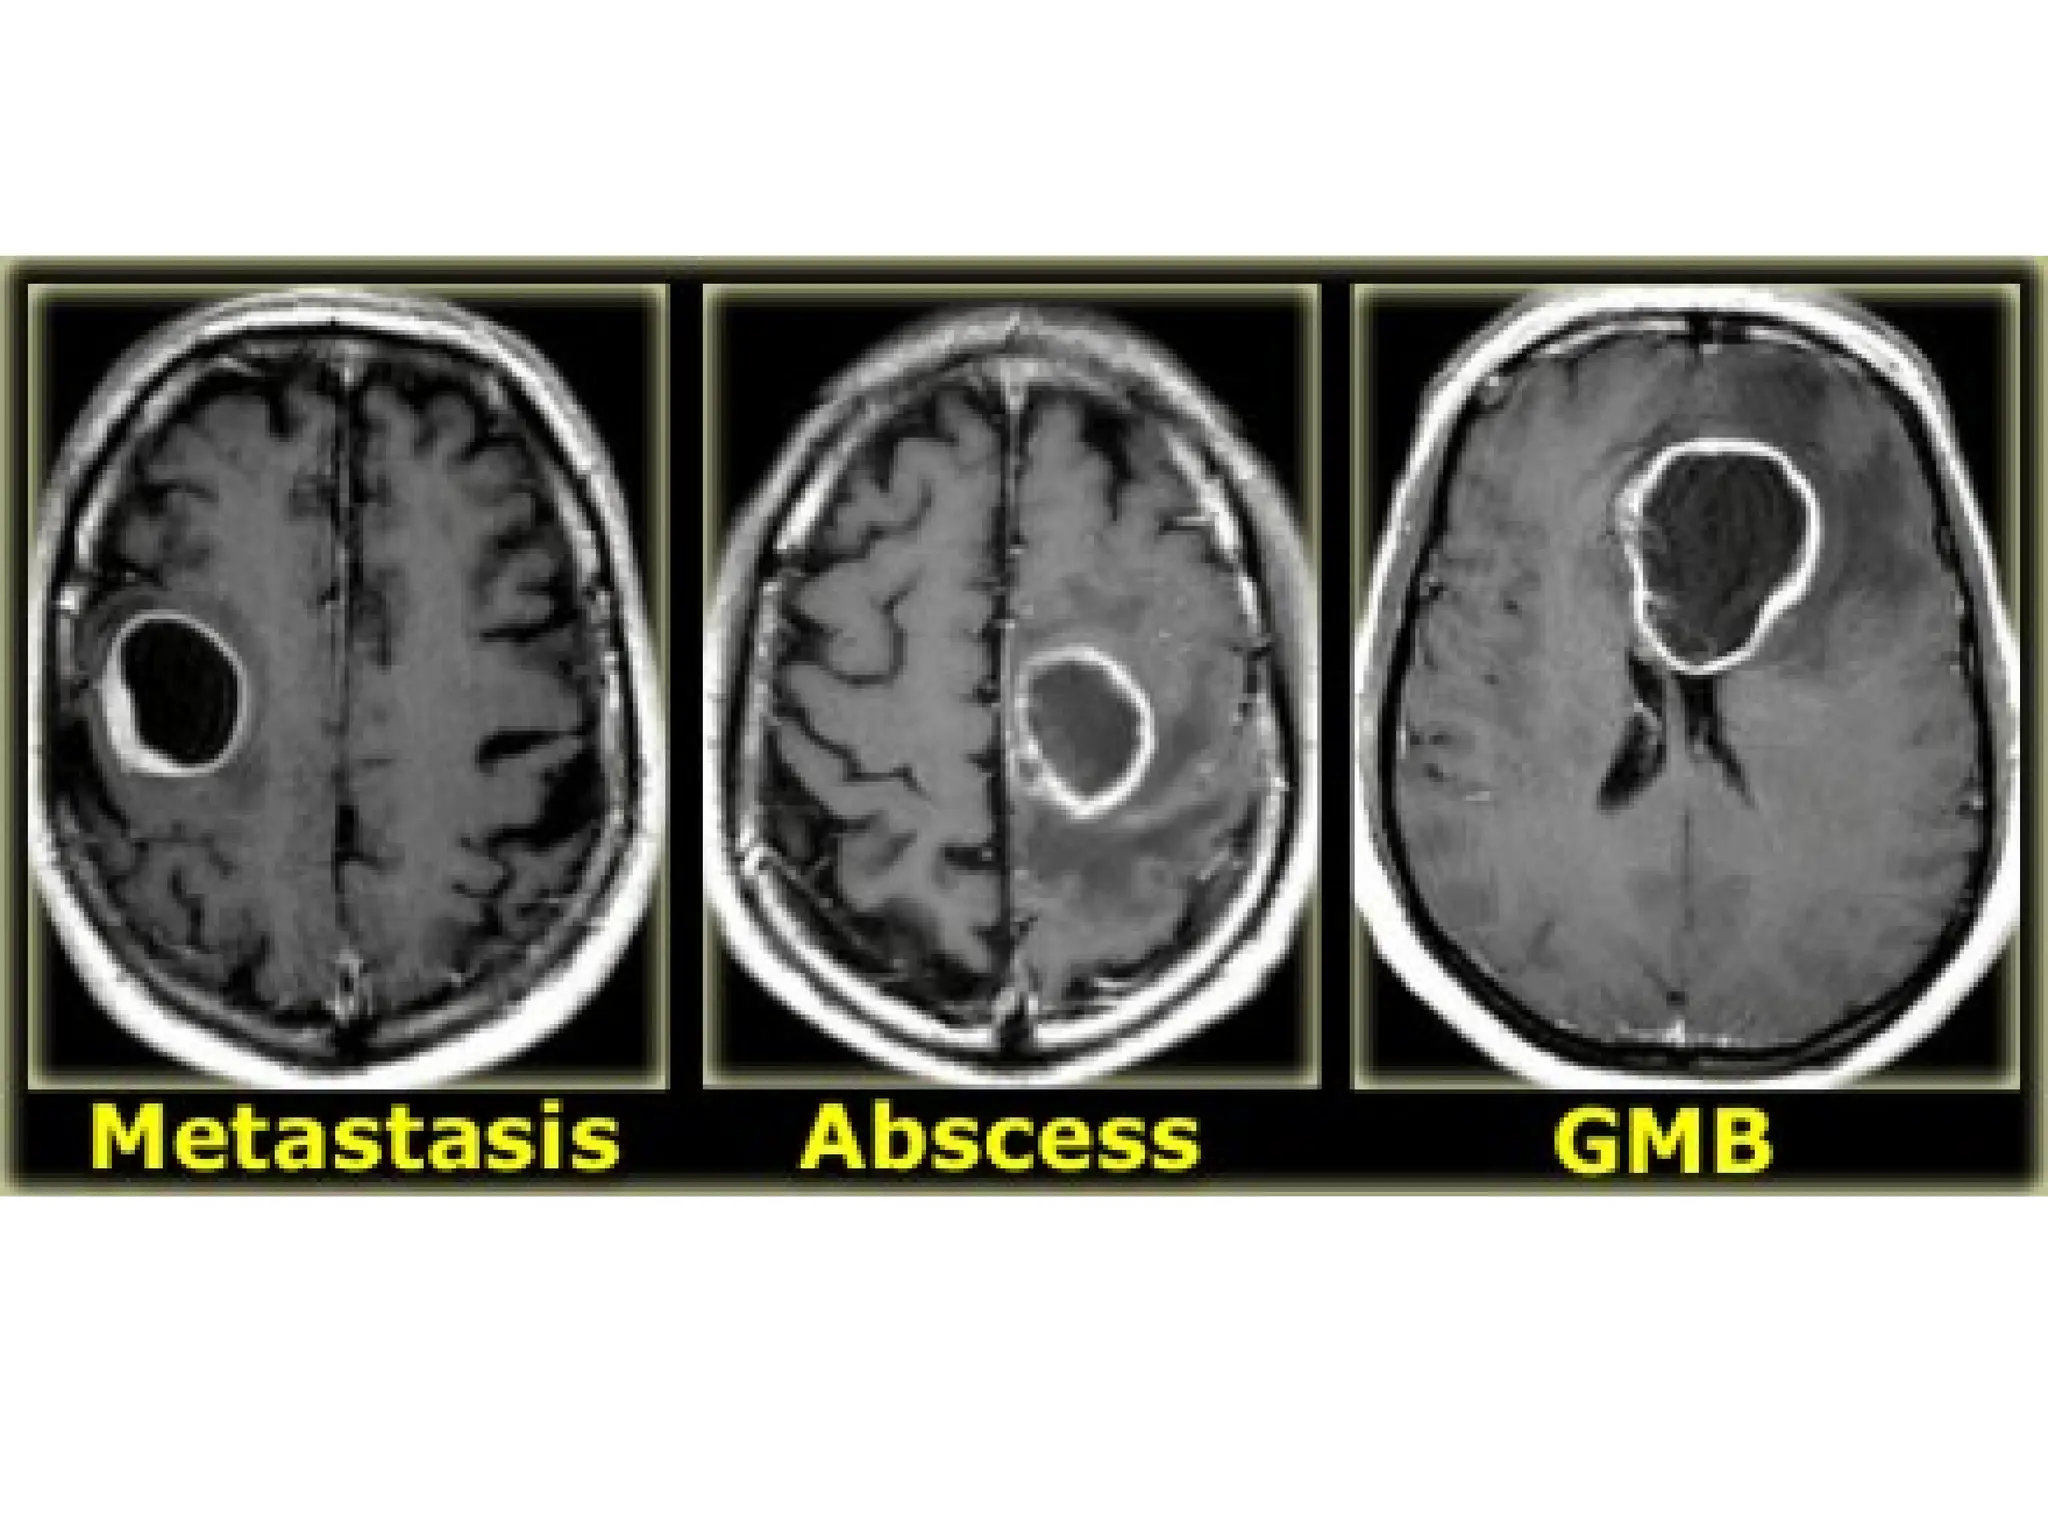

Multifocal disease

• Multiple tumors in the brain usually indicate metastatic disease.

• Primary brain tumors are typically seen in a single region, but

some brain tumors like lymphomas, multicentric glioblastomas

and gliomatosis cerebri can be multifocal.

• Some tumors can be multifocal as a result of seeding metastases:

this can occur in medulloblastomas (PNET-MB), ependymoma,

GBM and oligodendrogliomas.

LEFT: Metastases.